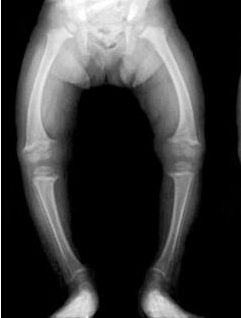

Рахит - это такое заболевание, при котором происходит нарушение опорно-двигательного аппарата на фоне нехватки витамина d . Рахит, симптомы которого обуславливаются также нарушением обмена фосфора и кальция . . .

Рахит у детей: признаки, симптомы и лечение, прогноз . . . Именно в это время, рахит может проявляться различной степенью тяжести . . . . фото . Нарастает анемическая гипоксия и понижение . . .